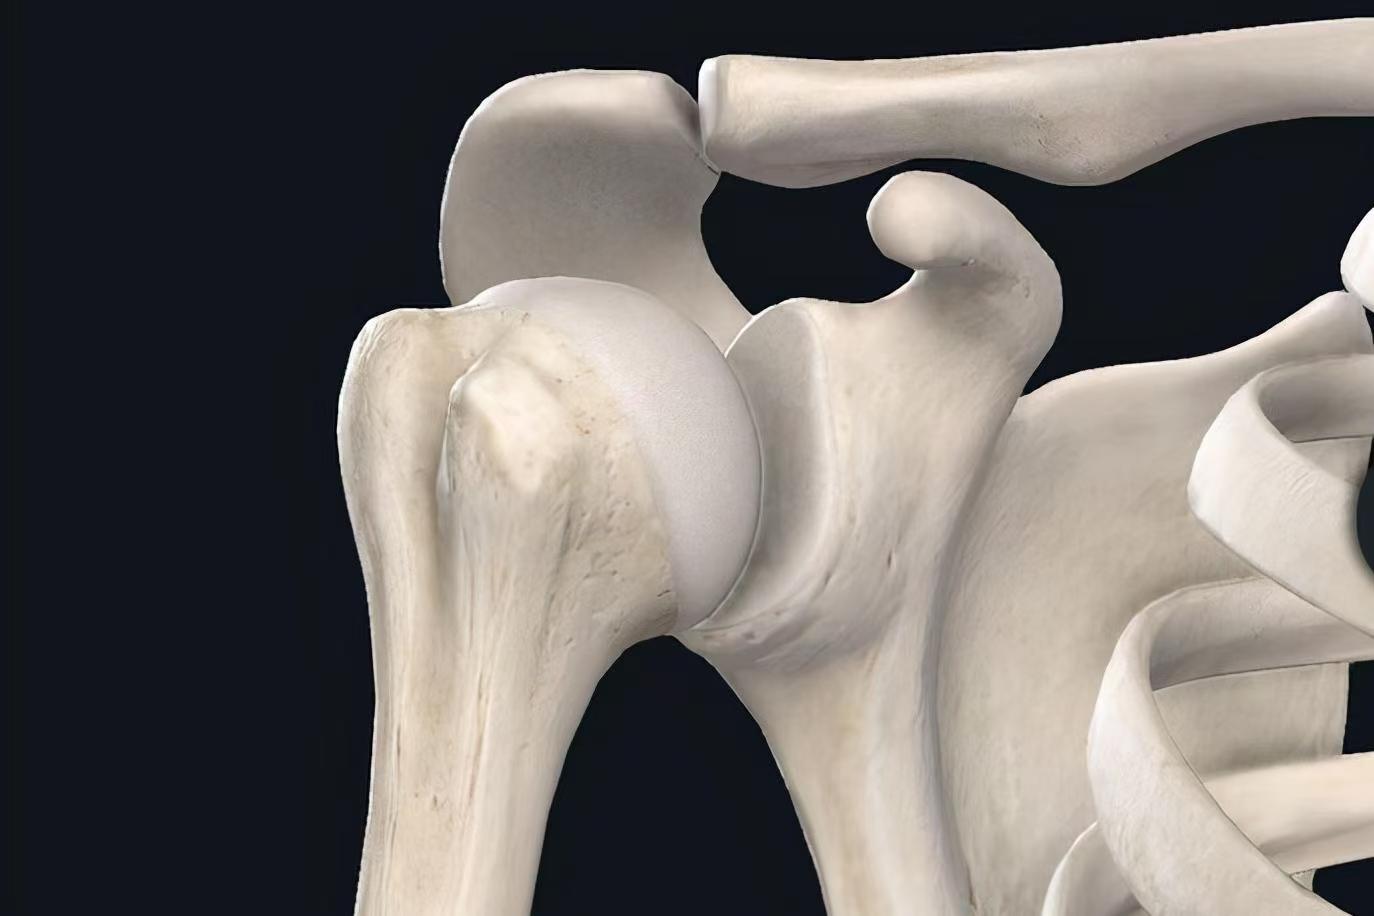

肱骨近端骨折 :跌倒、撞击、交通意外等暴力因素都可造成肱骨近端骨折。例如,跌倒时手掌或肘部先着地,可造成肱骨外科颈骨折;直接暴力打击肩部外侧或跌倒时肩部着地,会造成大结节骨裂与外科颈骨折。